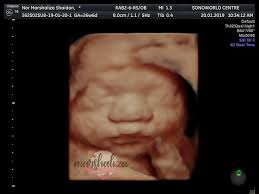

Ini antara sebab kenapa detail scan untuk bayi lebih penting dari scan 3d4d5d. Jika diikutkan pandangan pakar perubatan, sebenarnya tiada perbezaan signifikan yang akan dirasakan oleh wanita mengandung sama ada semasa mengandungkan anak lelaki ataupun perempuan. Dalam erti kata lain, anda mampu mengetahui jantina seawal usia janin pada umur 6 minggu kandungan. Bila dia tak boleh control mula la dia akan express emosi dia tu dengan macam macam cara. Kesimpulannya, entahlah nak pakai pendapat yang mana. • cadangan scan 4d dilakukan. Selalunya ini dinamakan skan anomali fetus dan digunakan juga untuk memeriksa posisi plasenta dan posisi bayi. Malah, anda tidak akan dapat menjelaskannya melalui perkataan, ianya merupakan satu perasaan yang membuatkan anda begitu bahagia.

Bila dia tak boleh control mula la dia akan express emosi dia tu dengan macam macam cara. Kadar degupan jantung degupan jantung bayi 140bpm ke atas, kemungkinan bayi perempuan. For more information and source,. Apabila sebut sahaja keterujaan menjadi 'first time parents', sudah pasti aspek keselamatan, pemakanan sehingga ke soal persiapan perlu diambil kira. Pada usia kehamilan 20 minggu, perbezaan antara lelaki dan perempuan menjadi lebih jelas dan lebih mudah dikesan kerana cecair ketuban yang banyak. Dalam erti kata lain, anda mampu mengetahui jantina seawal usia janin pada umur 6 minggu kandungan. Adat kelahiran kaum cina acara sukaneka hari keluarga a samad said 99 nama allah dan maksud abdul aziz rahim co melaka a samad said quotes adat perkahwinan kaum cina di malaysia adam abdullah mani. Malah, anda tidak akan dapat menjelaskannya melalui perkataan, ianya merupakan satu perasaan yang membuatkan anda begitu bahagia.

So, segalanya di tangan ilahi. Gambar scan bayi lelaki dalam kandungan foto cewek cantik. Ini antara sebab kenapa detail scan untuk bayi lebih penting dari scan 3d4d5d. Mujurlah aku masih boleh redha atas apa yang berlaku dan masih boleh menerima dan menyayangi anak lelakiku itu sepenuh hati. Baby boy gambar scan jantina bayi perempuan. Selalunya pengiraan dibuat berdasarkan tarikh konsepsi berlaku. Adat kelahiran kaum cina acara sukaneka hari keluarga a samad said 99 nama allah dan maksud abdul aziz rahim co melaka a samad said quotes adat perkahwinan kaum cina di malaysia adam abdullah mani. Tetapi, harga yang ditawarkan sekarang hanya rm25.00 sahaja. Ianya juga turut dikenali sebagai ramzi's method. Itu pun bergantung kepada kemahiran doktor yang melakukan scan, mesin ultrasound yang digunakan dan posisi bayi dalam rahem. Kesimpulannya, entahlah nak pakai pendapat yang mana. Cara mengetahui jantina bayi dalam kandungan menjadi ibu bapa untuk kali yang pertama adalah saat yang paling manis dan menggembirakan bagi pasangan yang berkahwin. Perasaan teruja apabila bakal menimang cahaya mata memang tidak dapat digambarkan.